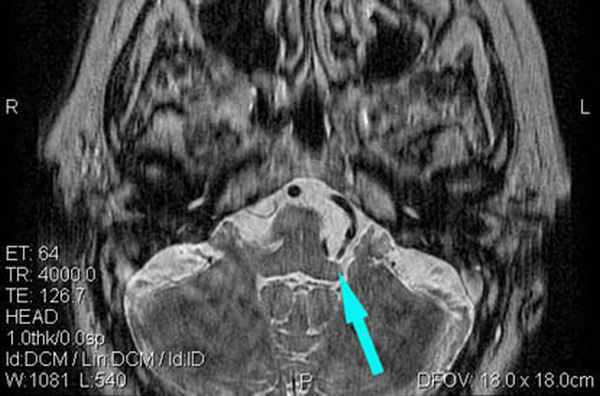

Определяются признаки компрессии лицевого нерва около ствола головного мозга крупным артериальным сосудом – позвоночной артерией (указано стрелкой).